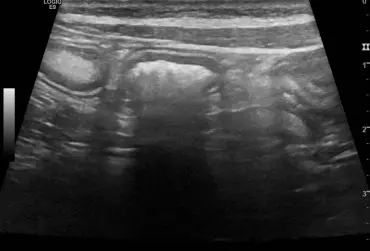

U 8-letniego niekastrowanego owczarka niemieckiego wykryto obecność kilku guzków skórnych widocznych na kończynach i na nosie. Badanie cytologiczne nie było jednoznaczne. W badaniu histopatologicznym jednego z usuniętych guzków stwierdzono obecność masy kolagenowej z niewielką ilością komórek zajętych głębokim, ropnym zapaleniem skóry. Po roku wykonano badanie ultrasonograficzne układu moczowego z powodu krwiomoczu i pogorszenia się stanu ogólnego psa. Wykryto liczne torbiele w obu nerkach o nietypowej strukturze. Na podstawie wyników badań postawiono rozpoznanie zespołu gruczolakoraka torbielowatego nerek i guzków włóknistych skóry (ang. renal cystadenocarcinoma and nodular dermatofibrosis – RNCD).